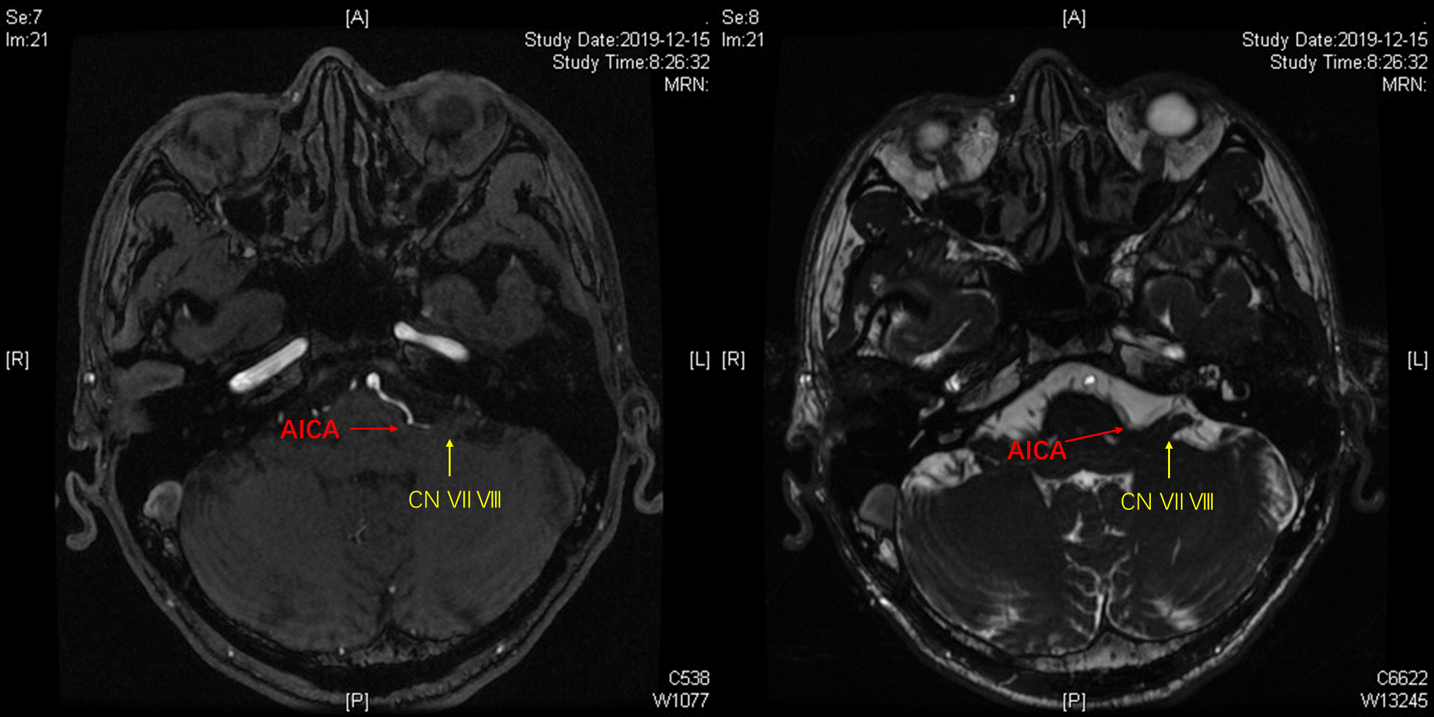

术前3D-TOF序列见左侧小脑前下动脉AICA从基底动脉发出,并弯曲成袢。

TOF序列及FIESTA序列见AICA向桥脑延髓沟方向弯曲,并与REZ区关系密切。

神经内镜经绒球下入路到桥小脑角区,可见AICA弯曲成袢压迫面神经出脑干处,与影像学所见一致。